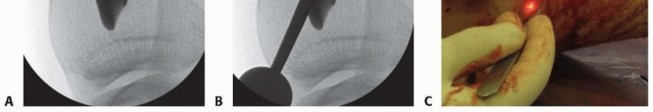

### FIG 4 • Clinical and fluoroscopic examples demonstrating usage of a guidewire to determine tibial anatomic axis and appropriate start site. A. Guidewire placed along tibial crest. B. Correlating fluoroscopic AP view showing guidewire at the medial aspect of the lateral tibial spine. Lateral parapatellar Fractures at the transition between metaphysis and diaphysis The lateral parapatellar approach allows for guidewire and nail placement in the more lateral position, which is beneficial in countering the valgus deformity associated with these fractures. It also allows intramedullary nailing in the familiar hyperflexed knee position. The semiextended position assists for reduction of the flexion deformity associated with these fractures. The limited or formal medial parapatellar may be used if the surgeon is unfamiliar with the suprapatellar approach and special instrumentation is not available. If the suprapatellar approach is being performed, a superomedial or superior midline is used and special instrumentation is required. All of the surgical approaches are performed with the knee in the semiextended position. 553 ## TECHNIQUES -

--- - TECH FIG 4 • A. Marking the skin along the crest can assist in aligning the guidewire with the path of the intramedullary canal and lessen the need for fluoroscopic guidance. B. Ideal proximal extra-articular start site as seen on lateral fluoroscopic image; this is near the articular margin. C. An ideal insertion vector approaches a parallel path with anterior cortex and minimizes the likelihood of fragment extension with seating of the nail. The starting guidewire is placed on the skin and radiographically aligned with the anatomic axis and in line with the lateral tibial spine on a true AP fluoroscopic image. The skin can be marked along the guidewire path to allow visualization of the anatomic axis without fluoroscopy ( TECH FIG 4A). The appropriate surgical approach is performed. The knee is maximally flexed, and the guidewire is aligned with the anatomic axis of the tibia. Typically, achieving an appropriate insertion vector will require the wire to be pushed against the patella or the peripatellar tissues. The anterior tibial crest is palpated for frontal plane wire alignment. Lateral plane fluoroscopy is necessary to place the wire at the proximal and superior aspect of the “flat spot” and near parallel with the anterior tibial cortical line ( TECH FIG 4B). The guidewire is directed 8 to 10 cm into the metaphysis. Guidewire position is verified in the AP and lateral planes. The frontal plane wire position should be in line with the anatomic axis and proximally should be just medial to the lateral tibial spine. Lateral alignment should be nearly parallel with the anterior tibial cortex, and all efforts should be made to avoid a posteriorly directed vector ( TECH FIG 4C). Creating and Reaming the Starting Hole The opening reamer (matching the proximal nail diameter) is introduced via a tissue sleeve and inserted while carefully maintaining knee hyperflexion and biplanar alignment. If the knee is allowed to extend or posterior pressure is not maintained on the tissue sleeve, the starting hole will become enlarged anteriorly, and the proximal anterior cortex will be violated. Imprecise reaming technique leads to anteriorization of the nail and violation of the proximal anterior cortex ( TECH FIG 5). Place a 15-degree bend 2 cm from the distal extent of the ball-tipped guidewire to allow for directional control during wire advancement. Alternatively, a straight ball-tipped guidewire can be used with an intramedullary reduction instrument (ie, a cannulated finger device), which can precisely direct the wire and simplify passage across the fracture. A ball-tipped guidewire is introduced into the proximal segment, and the knee is slightly extended for fracture reduction and instrumentation. 555